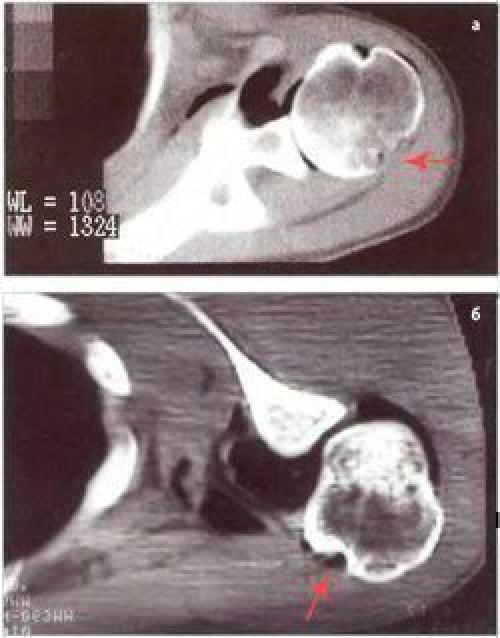

Повреждение Хилла-Сакса в виде импрессионного перелома задненаружного отдела головки плечевой кости

Таким образом, при компьютерной артропневмотомографии у всех пациентов с острой передней посттравматической нестабильностью плечевого сустава выявляют рентгенологические признаки классического повреждения Банкарта — отрыв суставной губы с капсулой плечевого сустава от передненижнего края суставного отростка лопатки и повреждения Хилла-Сакса — хондральный или компрессионный перелом головки плечевой кости.

Рентгенологические признаки рецидивирующей нестабильности отличаются большей поливалентностыо, что объясняется хроническим характером патологии. Так, у пациентов с большим количеством вывихов дегенеративные изменения в суставной губе и капсуле показывают высокую диагностическую точность выявленных рентгенологических признаков, что подтверждается при последующем артроскопическом исследовании плечевого сустава у данных пациентов.